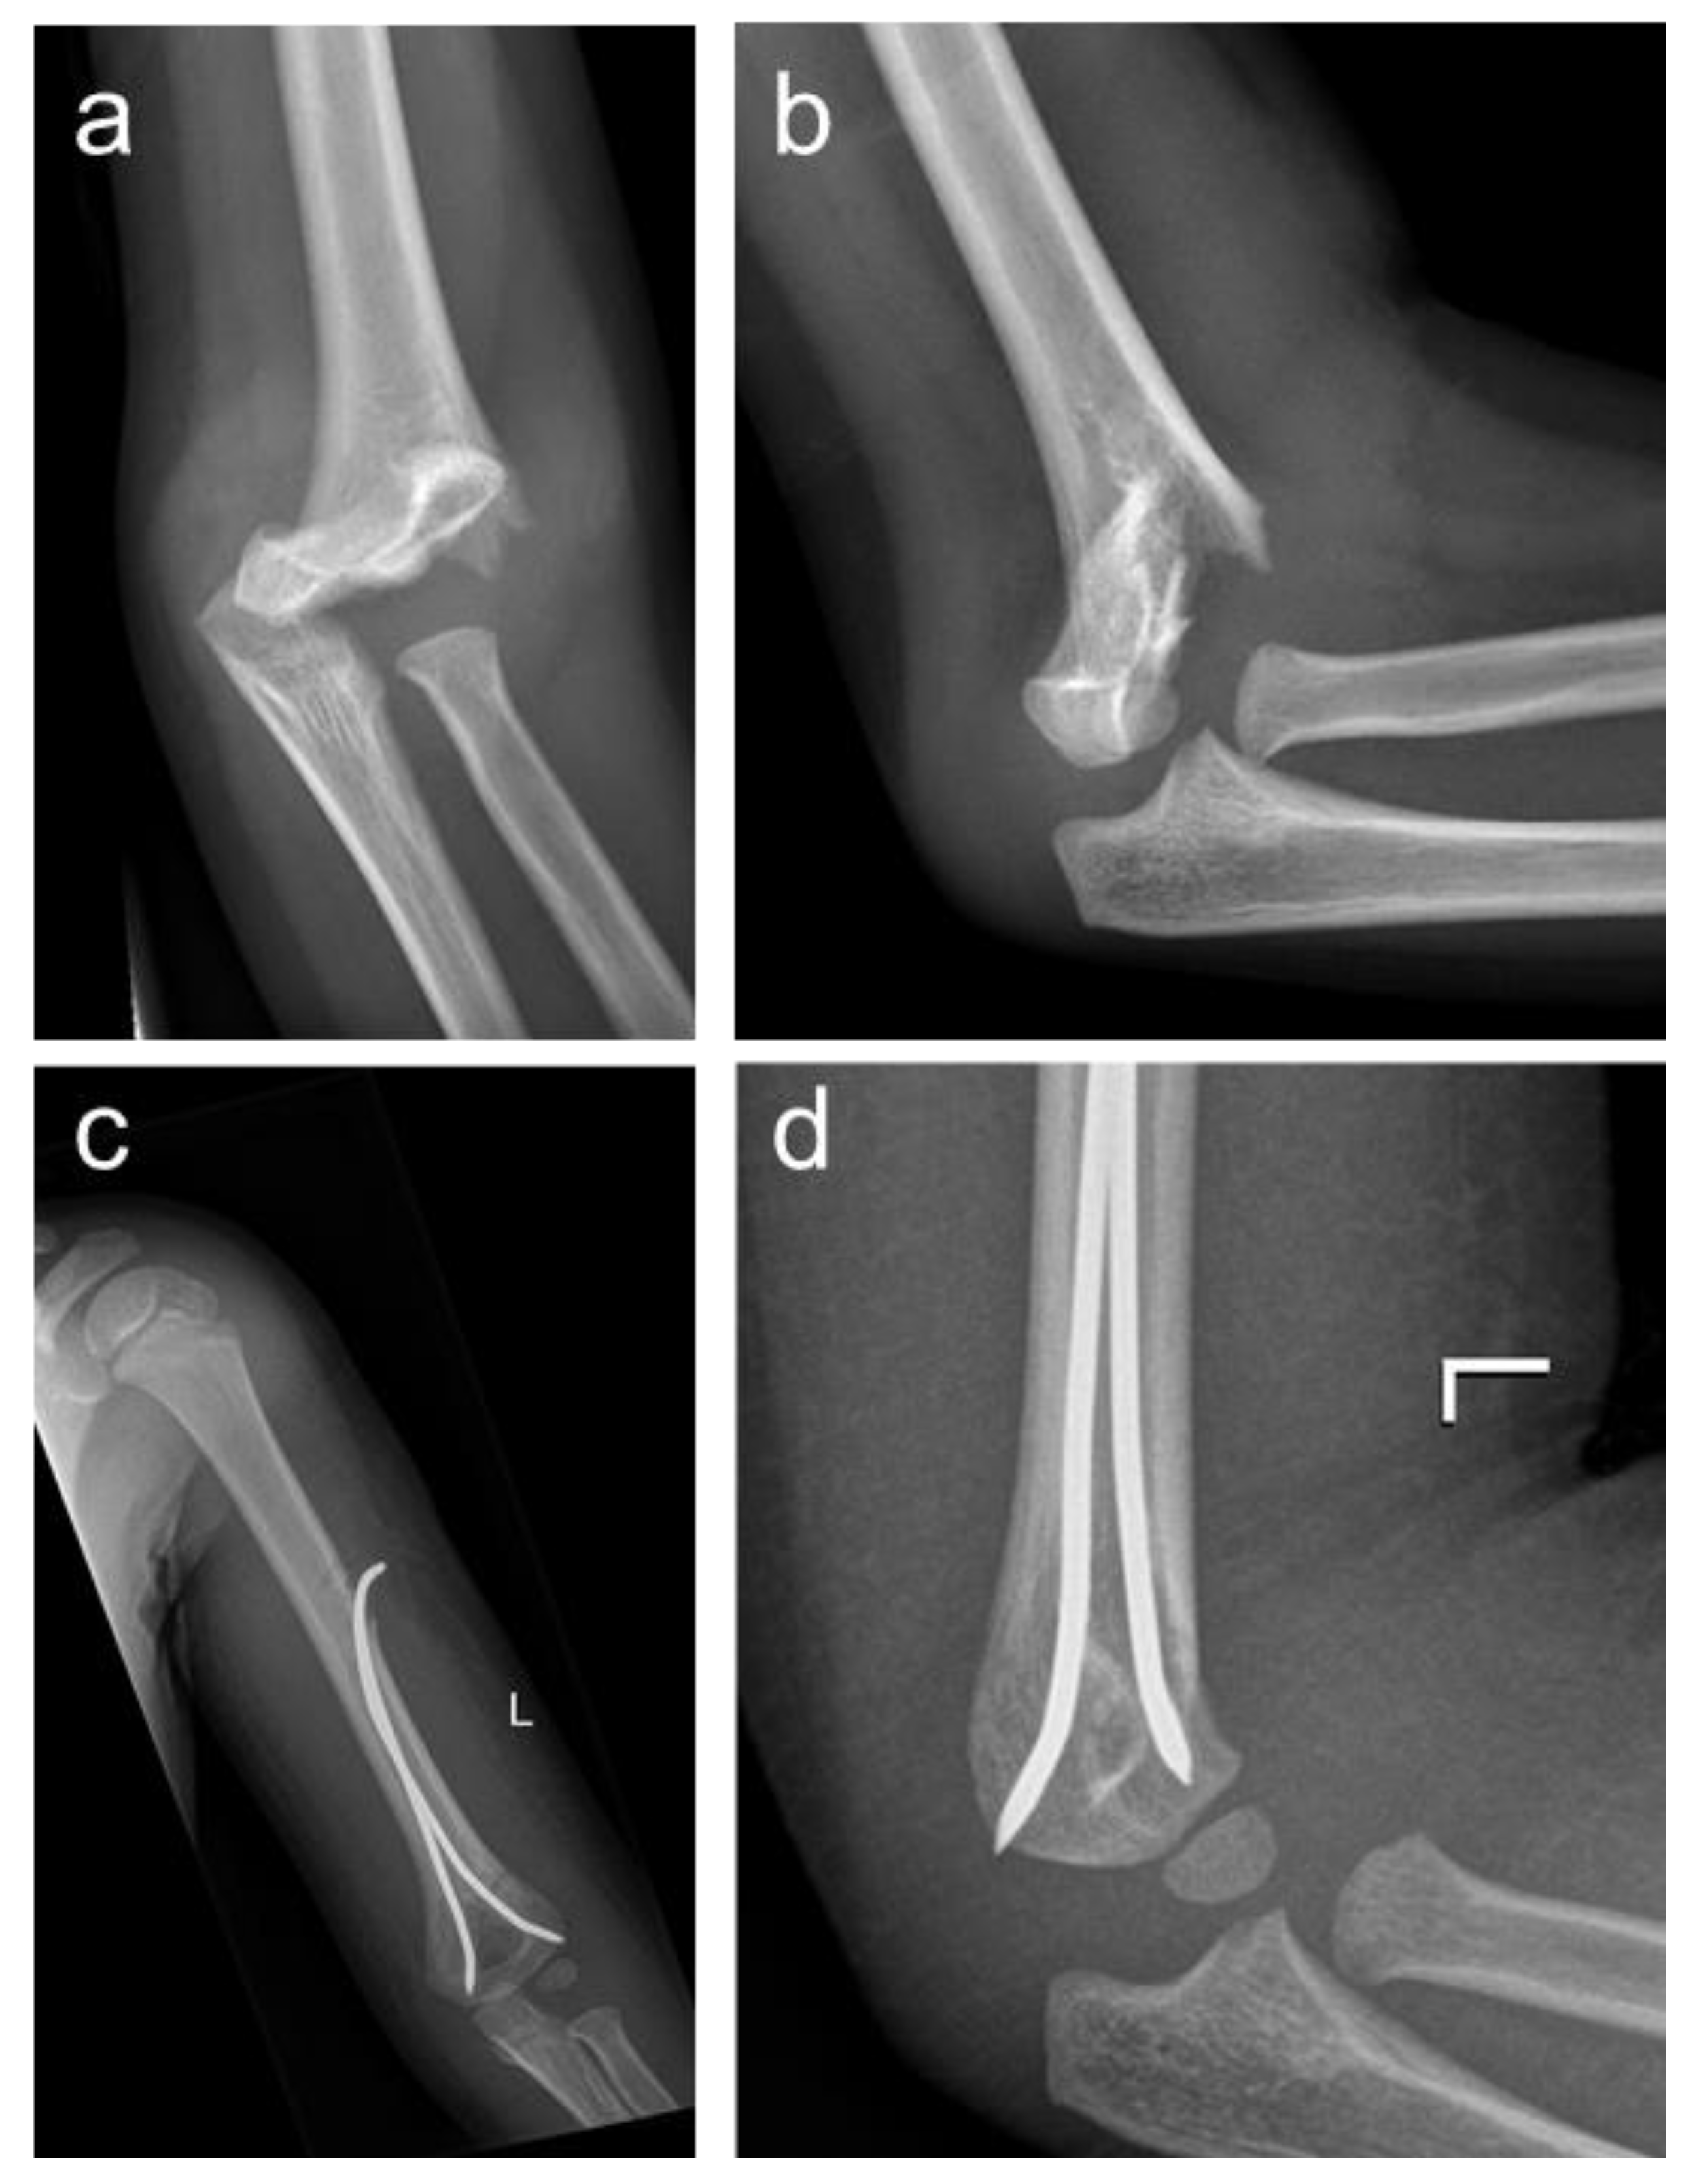

2.2. Surgical Technique

2.2.1. Closed Reduction

2.2.2. Retention by Antegrade Nailing (AN)

2.2.3. Retention by Percutaneous crossed Pinning (PCP)